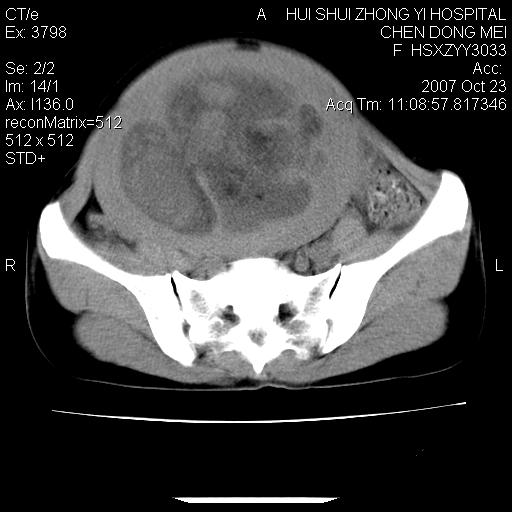

标题: CT10156:女.43岁,发现中下腹部包都块2年 [打印本页]

标题: CT10156:女.43岁,发现中下腹部包都块2年

发现中下腹部包都块2年。2年来月经不规律。

腹腔巨大软组织密度影,边缘光滑,包膜完整,内囊变坏死。腹膜后及盆腔内淋巴结肿大。结合病史考虑卵巢癌可能性大。

病变巨大,呈囊实性改变,包膜较厚且完整,内见分膈,周围脏器明显受压移位,病变与左侧附件关系密切,考虑来源左侧附件的囊腺瘤,不除外癌变可能;畸胎瘤可能性较小。

病变巨大,呈囊实性改变,包膜较厚且完整,内见分膈,周围脏器明显受压移位,病变与左侧附件关系密切,考虑来源左侧附件的囊腺瘤,盆腔内见肿大淋巴结,不除外癌变可能。

病变巨大,呈囊实性改变,包膜较厚且完整,内见分膈,周围脏器明显受压移位,病变与左侧附件关系密切,考虑来源左侧附件的囊腺瘤,不除外癌变可能